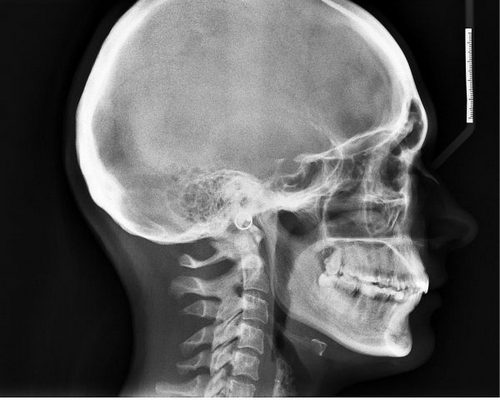

Лечение головной боли, как и любое другое, начинается с постановки диагноза (в основном с помощью мрт при головных болях или томография) и определения причины.